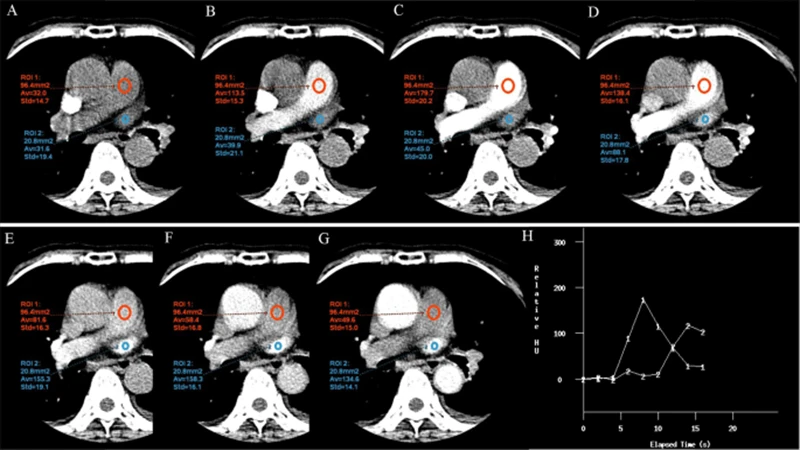

- Scan Timing: This is the most critical element. The technologist must time the start of the scan perfectly to coincide with the moment the contrast-filled blood reaches the specific arteries or veins of interest. This "bolus tracking" is often done using a monitoring scan that detects when the contrast arrives at a target location.